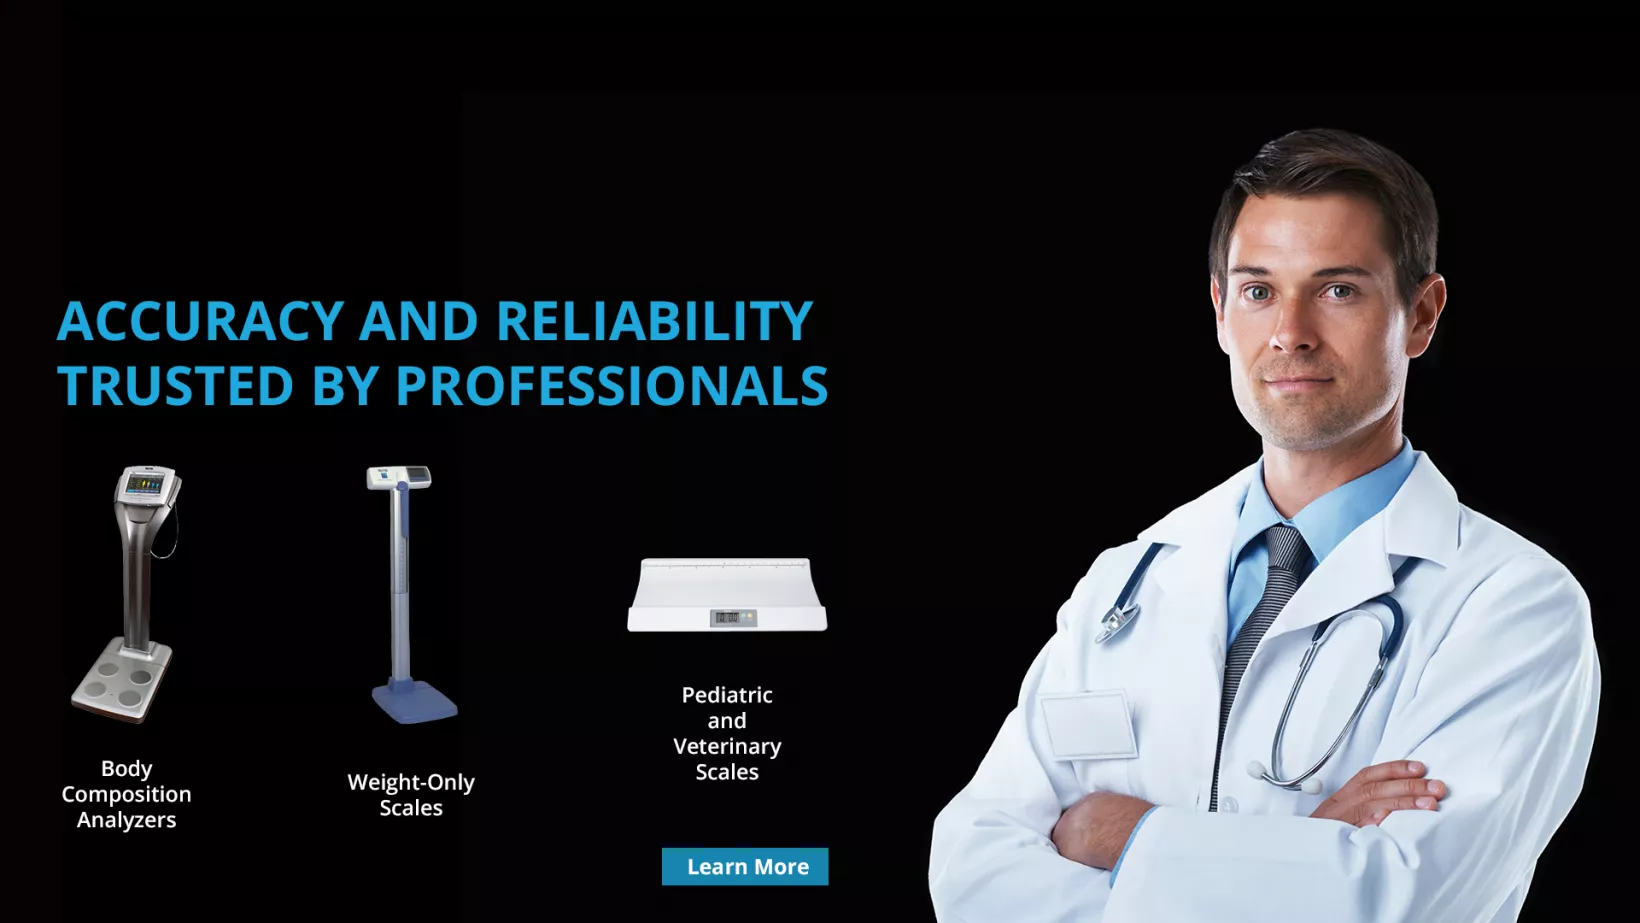

Professional Scales

Tanita's line of US Food & Drug Administration (FDA) approved professional scales incorporate state-of-the-art #technology within the most user-friendly package in the industry. Our Legal for Trade professional product line provides invaluable information to: clinical researchers #and medical experts, point-of-care physicians in the Acute Care, Long-Term Care, Pediatric and Veterinary practices, sports

coaches (wrestling, #training rooms), #and scientists working in the fields of obesity, cardiology, physiology, diabetes, nutrition, chiropractic, and rehabilitation therapies. These monitors and doctor scales, physician scales also help doctors by improving patient understanding and compliance in treatment programs and provide greater accessibility for patients, as well as, increased portability and accuracy

for healthcare professionals in the geriatric and bariatric fields.

Tanita's wide variety of professional analyzers provide a detailed full body and segmental body composition analysis - weight, impedance, body fat percentage, body fat mass, body mass index (BMI), fat free mass, estimated muscle mass, total body water, and basal metabolic rate (BMR) for the entire body by using Bioelectrical Impedance Analysis (BIA) or Direct-Segmental Bioelectrical Impedance Analysis (DSM-BIA) technology (two of the most thorough and reliable ways to measure body

composition). All scales are built with Tanita's high standards, and many products feature a convenient carrying case, height rod, USB (Type B) & RS232 outputs, software, and a remote display, guaranteeing #long-lasting performance, even in the most demanding healthcare environments.

Tanita's best-selling professional line #of high-capacity scales include pediatric/pediatrician (baby, neonatal) scales, physician scale, hospital scales, digital column scales, wheelchair scales, handrail and beam scales, NTEP scales, food/restaurant scales and a collection of laboratory scales. The lab scales are used for a #variety of diagnostic measurements, including hypertension, metabolic syndrome,

childhood obesity, and visceral fat detection used to identify bariatric surgery cases and those who may be at a higher risk for cancer.

As the world-leader in providing scales for healthcare professionals, Tanita scales are more affordable and convenient than DEXA (dual energy X-ray absorptiometry) or hydrostatic weighting, yet offer accuracy used in measuring multiple frequency BIA. Our scales provide insight into such indicators as weight loss, caloric intake, diet and #exercise, adipose tissue, and total body water (intracellular and extracellular water) in both pounds and kilograms

- making them useful for fitness gyms and clubs as well. #Some models feature stadiometers (height rods), are EMR compatible, are Welch Allen compatible, and wireless output, but all are ISO 9001 certified. TANITA is the only scale trusted by the NCAA Wrestling Championships, USA Wrestling, the Midlands Wrestling Championships, the Reno Tournament of Champions, the Dan #Gable

International Wrestling Institute #and Museum as well as countless other tournaments, programs and organizations worldwide